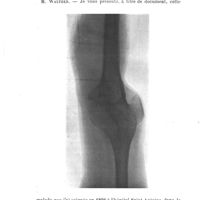

0429 - Page 421 - Séance du 12 mars 1913. Présentations de malades. Résection du genou datant de vingt-six ans. Etat actuel. Radiographie, M. Schwartz (Edouard)0429 - Page 421 - Séance du 12 mars 1913. Présentations de malades. Résection du genou datant de vingt-six ans. Etat actuel. Radiographie, M. Schwartz (Edouard)